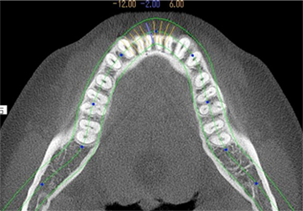

レントゲン撮影・CT撮影・口腔内Scan ・シュミレーションソフトによるプランニング

インプラント予定部位の骨の状態、周囲組織の状態を診査します。CTを用いることで多角的に診断することができます。当院では最新の歯科用コーンビームCTを設置し、低被爆を実現しています。

当院では最新のドイツKavo 社製のCTを設置しています。

低被爆で細かな診断と埋入シュミレーションを行い診断をしております。